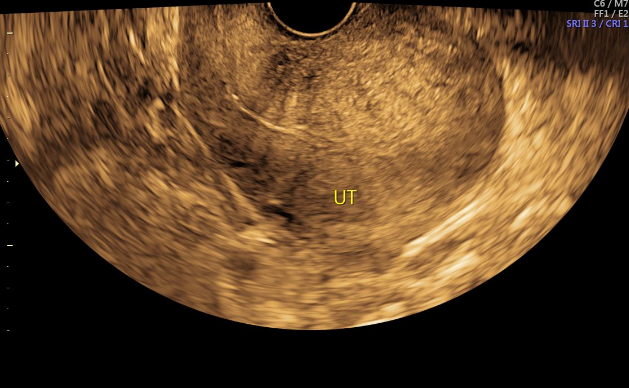

2024-9-12经阴道妇科彩超提示:子宫呈后位,长径69mm,前后径55mm,横径65mm,后壁肌层回声不均,见细小的增强回声区和低回声区交织混杂,内膜厚3mm,光整,内膜线前移,双附件区未见占位病变,子宫直肠窝内未见液性暗区,CDFI未见明显血流信号。